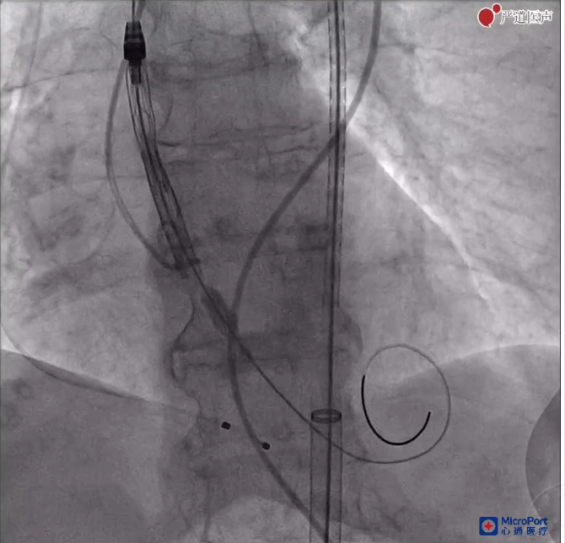

由于该患者轻度横位心,且为前后位二叶瓣,输送系统跨瓣存在一定困难,与会专家和术者一致考虑使用Snare技术。在右冠窦猪尾的指示和圈套器的辅助下,瓣膜输送系统输送至窦底,开始释放。在确认位置后,术者保持当前张力,快速一次性释放。

释放